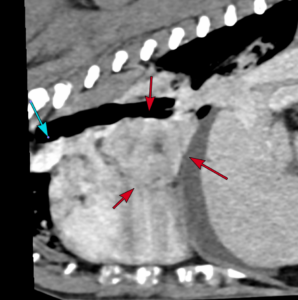

Barney, a 9 year old Soft-Coated Wheaten Terrier, presented to Northern Ireland Veterinary Specialists (NIVS) due to a 3 month history of refractory ascites and documentation of a cardiac mass by his primary vets, Banbridge Pet Vets. Investigations at NIVS by Julie Hamilton Elliott (RCVS and EBVS® Specialist in Veterinary Cardiology) confirmed the cardiac mass was causing compression of caudal vena cava entering the right atrium. This was resulting in Budd-Chiari syndrome with subsequent hepatic venous congestion and ascites. Computed Tomography (CT), performed for surgical planning, confirmed a large 4×3.7cm mass located between the right and left atrium with no evidence of secondary metastatic disease.

The minimally invasive, fluoroscopic-guided procedure involved accessing both the right jugular and left femoral veins. The location and extent of the mass was first determined by a contrast angiographic study. A series of catheters and guidewires were then used to deploy a woven Nitinol stent extending from the caudal to the cranial vena cava, through the right atrium. Repeat angiography revealed improved caudal vena caval flow and Barney recovered uneventfully. He was discharged the following morning.